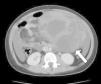

El estudio se completó con una tomografía computarizada que confirma la existencia de la masa abdominal sólido-quística de probable origen anexial izquierdo (21×16×13cm) que desplaza asas intestinales e importante líquido ascítico (fig. 2). El estudio hormonal mostró unos niveles séricos muy elevados de estradiol (196 pg/ml; vn: 19-144), con niveles inhibidos de hormona foliculoestimulante (< 0,3 mU/ml; vn: 2,5-10,2) y hormona luteinizante (<0,07U/ml; vn: 1,9-12,5), indicativos de inhibición del eje hipotálamo-hipófiso-gonadal y seudopubertad por producción exógena/tumoral de estradiol. También se encontraron muy elevados, como marcadores tumorales, los niveles séricos de inhibina A (469pg/ml; vn: 3,5-31) y B (>944pg/ml; vn: 93-352) y antígeno carcinoembrionario-125 (291U/ml; vn: <30,2). Otros marcadores tumorales (gonadotropina coriónica beta, alfafetoproteína y antígeno carcinoembrionario) fueron negativos. Tras la extirpación quirúrgica completa, el estudio anatomopatológico es compatible con un tumor de células de la granulosa de tipo juvenil juvenil (TCGJ). Asimismo, se confirma la infiltración del líquido ascítico por el tumor. La paciente se clasifica como un estadio ii C de la clasificación de la Federación Internacional de Ginecología y Obstetricia, por lo que se inicia tratamiento quimioterápico con cisplatino, etopósido y bleomicina.